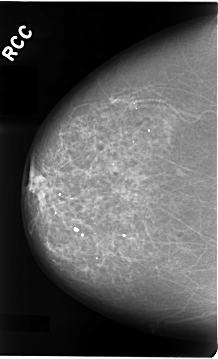

C_0028_1.RIGHT_CC

RIGHT_CC LINES 4664 PIXELS_PER_LINE 2832 BITS_PER_PIXEL 12 RESOLUTION 50 NON_OVERLAY